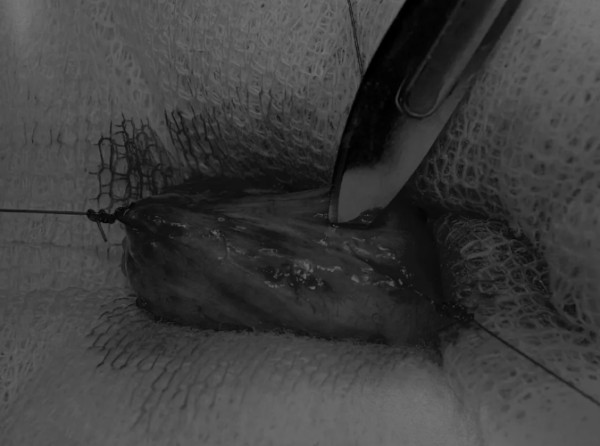

在中线开腹手术后,确定膀胱,将其取出并隔离(图1)。为了使膀胱持续暴露,可在膀胱中线两侧各放置一根固定缝线(图2)。

图2 在手术过程中,还需要另外两根固定缝线来保持膀胱切开术的膀胱边缘处于暴露状态

在牵引缝线之间选择血管扩张较差的区域用手术刀切开膀胱壁(图3)。在牵引缝合线之间用手术刀在血管不良的区域做切口。切开膀胱壁后,膀胱内的手术可按手术方案实施,例如取出结石(图4)。

图3 避开主要的膀胱血管,做一个尽可能小的切口